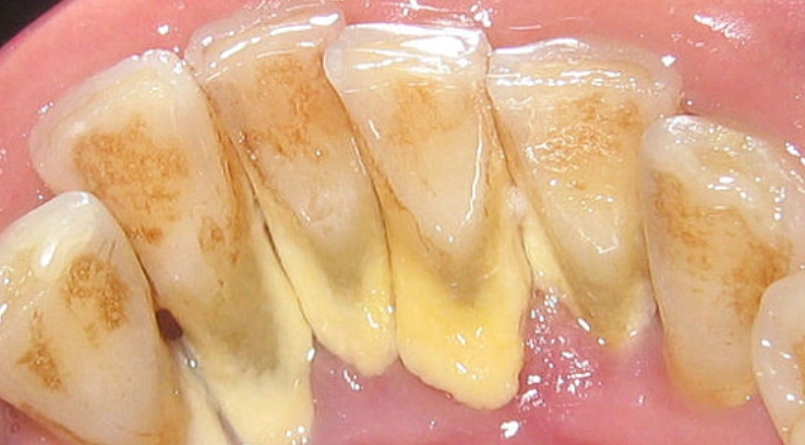

牙結石就是牙菌斑鈣化後的硬塊,通常堆積在牙齒和牙齦交界處,光靠刷牙很難清掉。洗牙機,也叫水牙線,用高壓水流沖洗這些死角。我自己發現,即使每天刷牙,牙縫後方還是會積一點黃色垢,那就是牙結石的前身。

牙結石如果不處理,會慢慢導致牙齦炎甚至牙周病。洗牙機能輔助清潔,但對於已經形成的硬塊,還是得靠牙醫的超音波洗牙。家用洗牙機更適合日常維護,防止新結石生成。